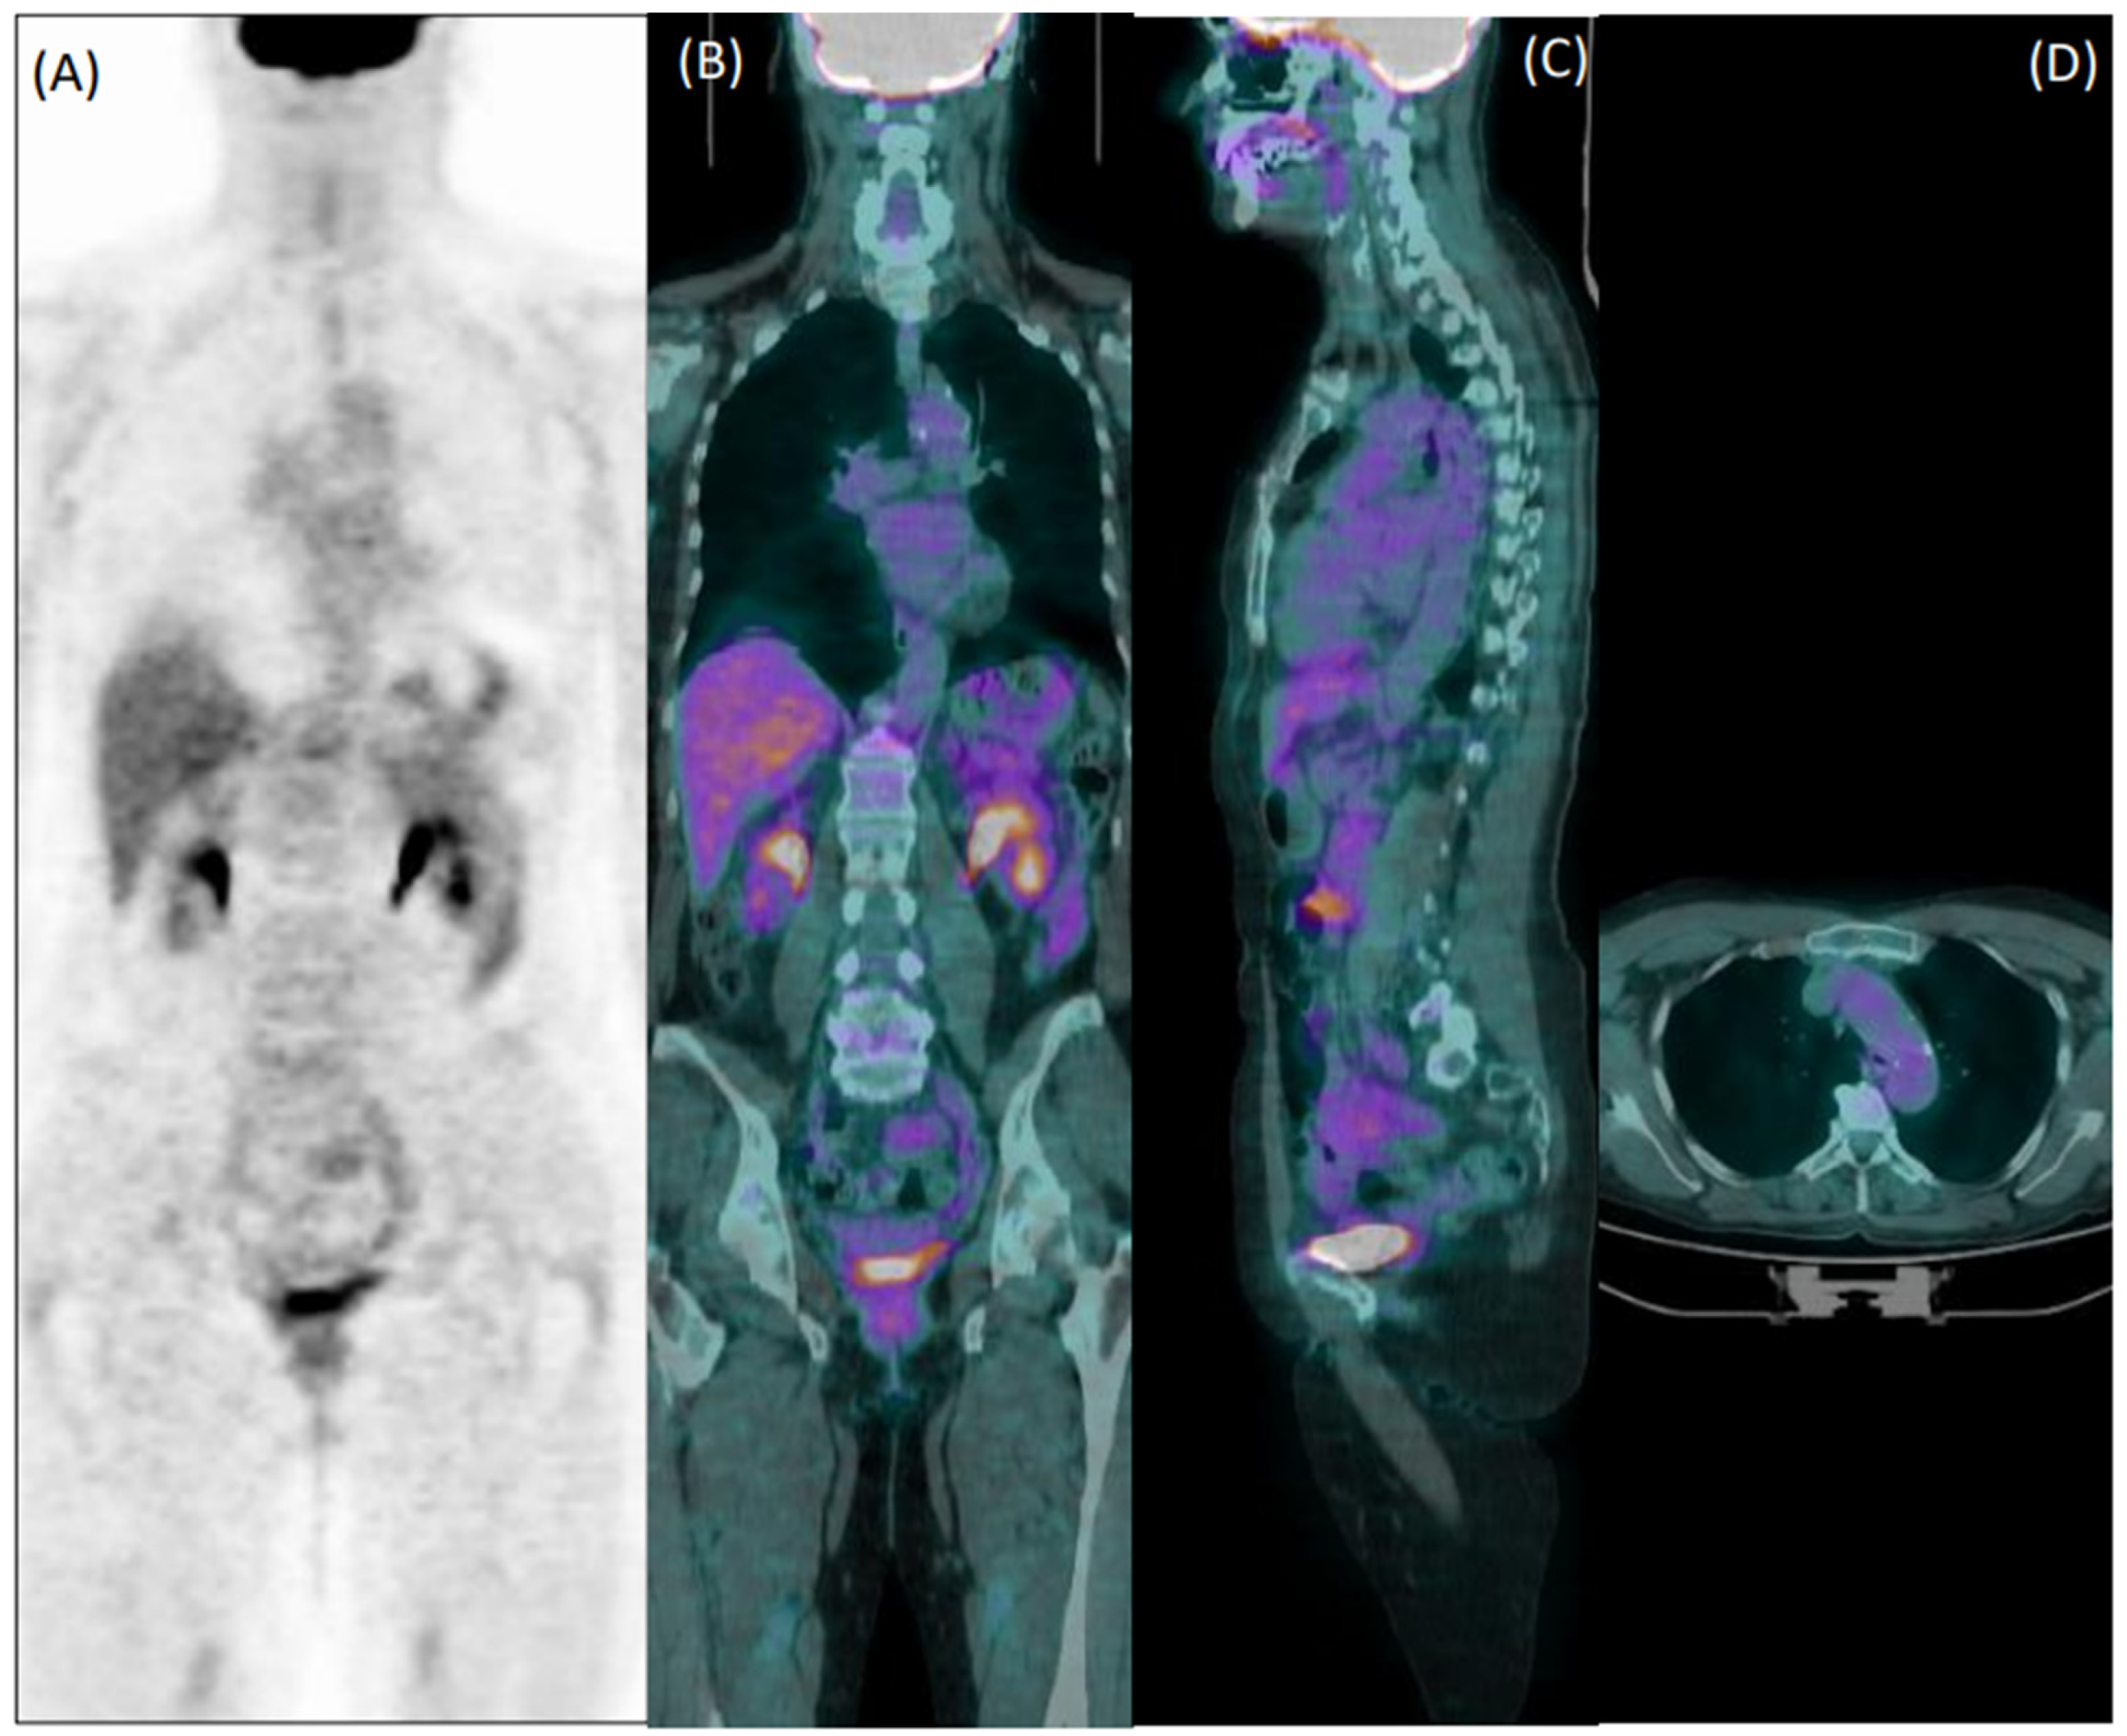

In total, 81 patients (29%) were clinically diagnosed with LVV. Reader 1 and reader 2 failed diagnosis in 76 patients (37 false negative and 39 false positive) and 92 patients, respectively (33 false negative and 59 false positive). Figure 1 and Figure 2 show examples of a true positive and a false positive PET exam. Among the 76 patients wrongly classified by reader 1, 51 were >65-years-old, 44 were overweight, 46 were taking steroids, 12 presented with hyperglycemia, 29 were early acquired, while in 26 patients, the acquisition was delayed, and 23 were scanned with P1.

Figure 2. Coronal [18F]FDG PET (A) and fused PET/CT coronal (B), sagittal (C), and axial (D) images of a 75-year-old female patient with diffuse articular pain and suspicion of vasculitis, not further confirmed during clinical follow-up. Images were evaluated as positive for increased uptake in the aorta, and both subclavian and iliac arteries by the experienced reader 1. Reader 2 evaluated the exam as negative.